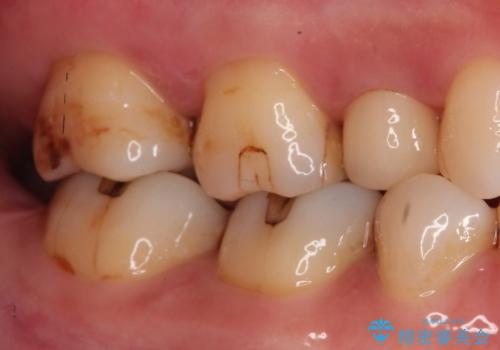

【セラミックインレー】虫歯の治療

- 虫歯を認めたため、セラミックインレーにて治療を行いました。

見た目も綺麗に修復することができ患者様には満足していただきました。

セラミックインレーの接着には必ずラバーダム防湿を行なっています。